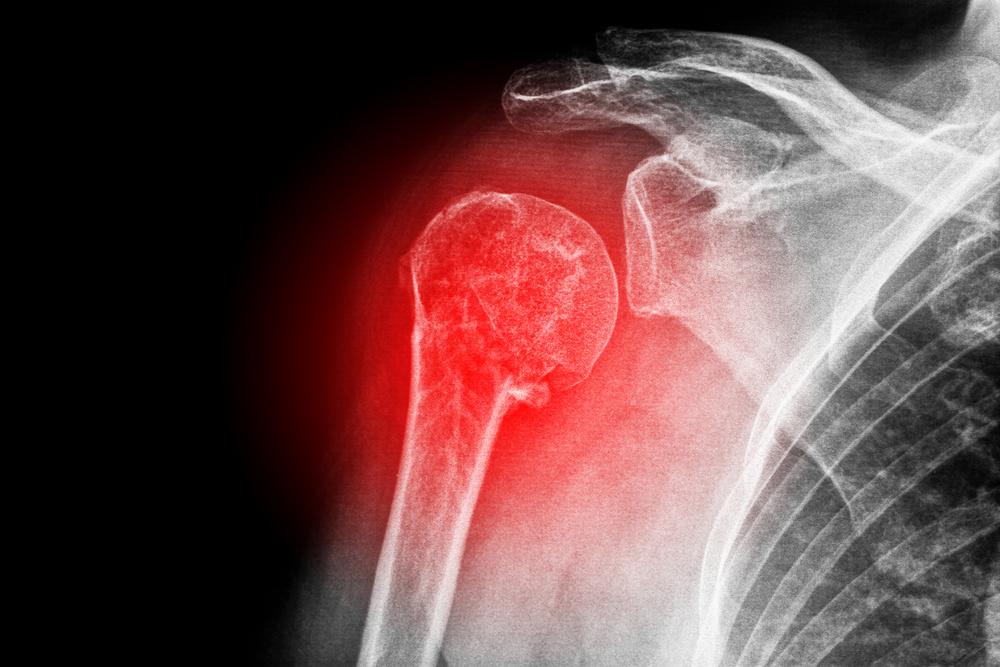

DISLOKASI

Dislokasi adalah suatu cedera yang terjadi pada tulang ketika tergesernya tulang pada sendi dari

tempatnya menyebabkan tulang tergeser dari

tempat sebenarnya, Dislokasi biasanya terjadi karena benturan tiba-tiba misalnya karena terjatuh, terpukul benda keras, atau cedera lainnya

Pada kasus cedera dislokasi pertolongan pertama yang dapat di lakukan yaitu pertama dengan memberikan tindakan dengan metode RICE disertai dengan tindakan pemasangan alat immobilisasi seperti bidai atau gips, Hal ini dilakukan untuk membuat ruang pada ligament yang mungkin rusak atau robek pada saat dislokasi. Apabila ligament terputus maka korban harus segera di bawa ke rumah sakit untuk di lakukan tindakan reposisi dan penyambungan ligament yang robek oleh dokter bedah.

REST

Pada tahap ini ketika terjadi cedera segera istirahatkan bagian tubuh yang mengalami cedera, hal ini bertujuan untuk mencegah bertambahnya keparahan cedera dan mengurangi perdarahan ke arah cedera. Waktu untuk

mengistirahatkan bagian cedera tergantung pada tingkat keparahan cedera (ringan – berat)

ICE

Pemberian es pada bagian cedera bermanfaat untuk membantu menyempitkan pembuluh darah (Vasokontriksi) untuk mengurangi perdarahan dan mencegah pembengkakan, menurunkan kepekaan syaraf sehingga mengurangi nyeri, serta mengurangi resiko kematian sel. Kompres es ini di lakukan dengan cara menempatkan es di dalam ice bag atau handuk kecil kemudian diletakkan di bagian cedera selama 10-15 menit. Kompres tidak boleh di lakukan terlalu lama karena dapat mengakibatkan kerusakan jaringan pada tubuh dan vasodilatasi berlebihan, jika penderita merasa kesemutan atau kulit terlihat pucat maka hentikan kompres es